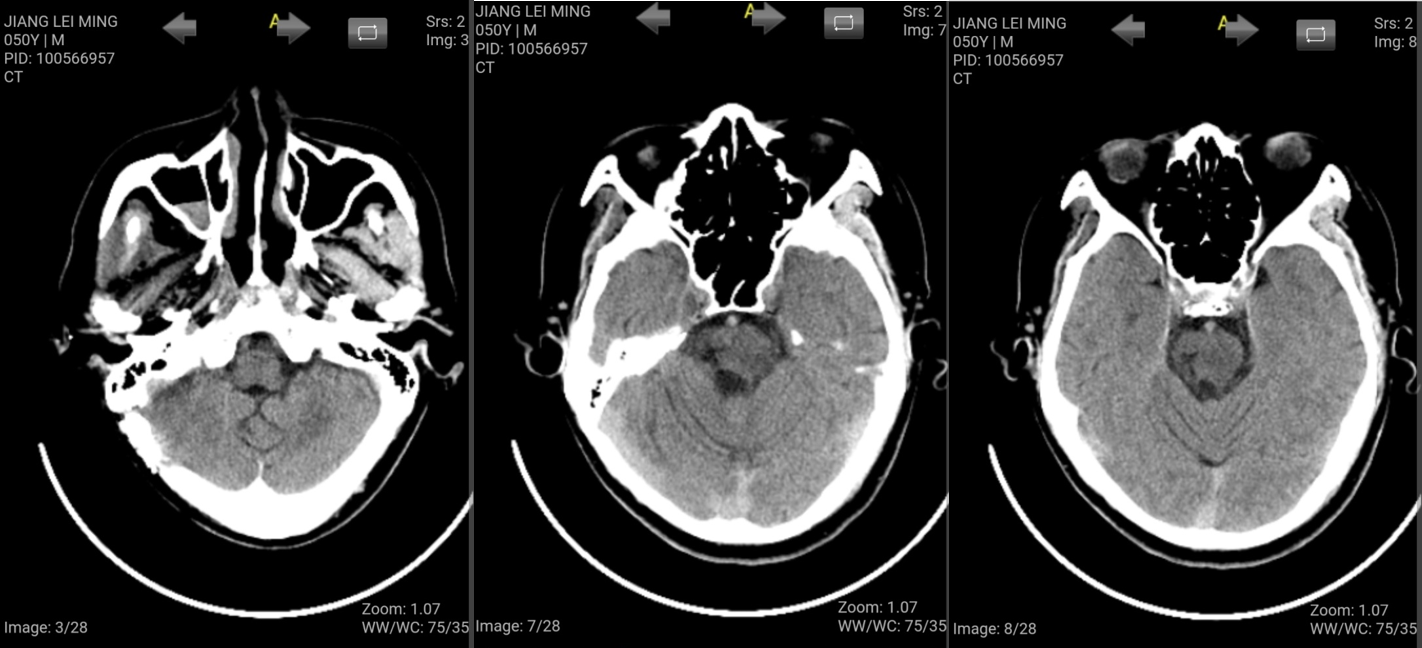

四月复查CT示出血区除外,脑干结构完好

术后6个月微信随访,患者神志清,思维敏捷,右侧肢体活动良好,左侧肢体已恢复至3-4级肌力,远端精细活动还不理想。

相信1年后恢复还会更好。